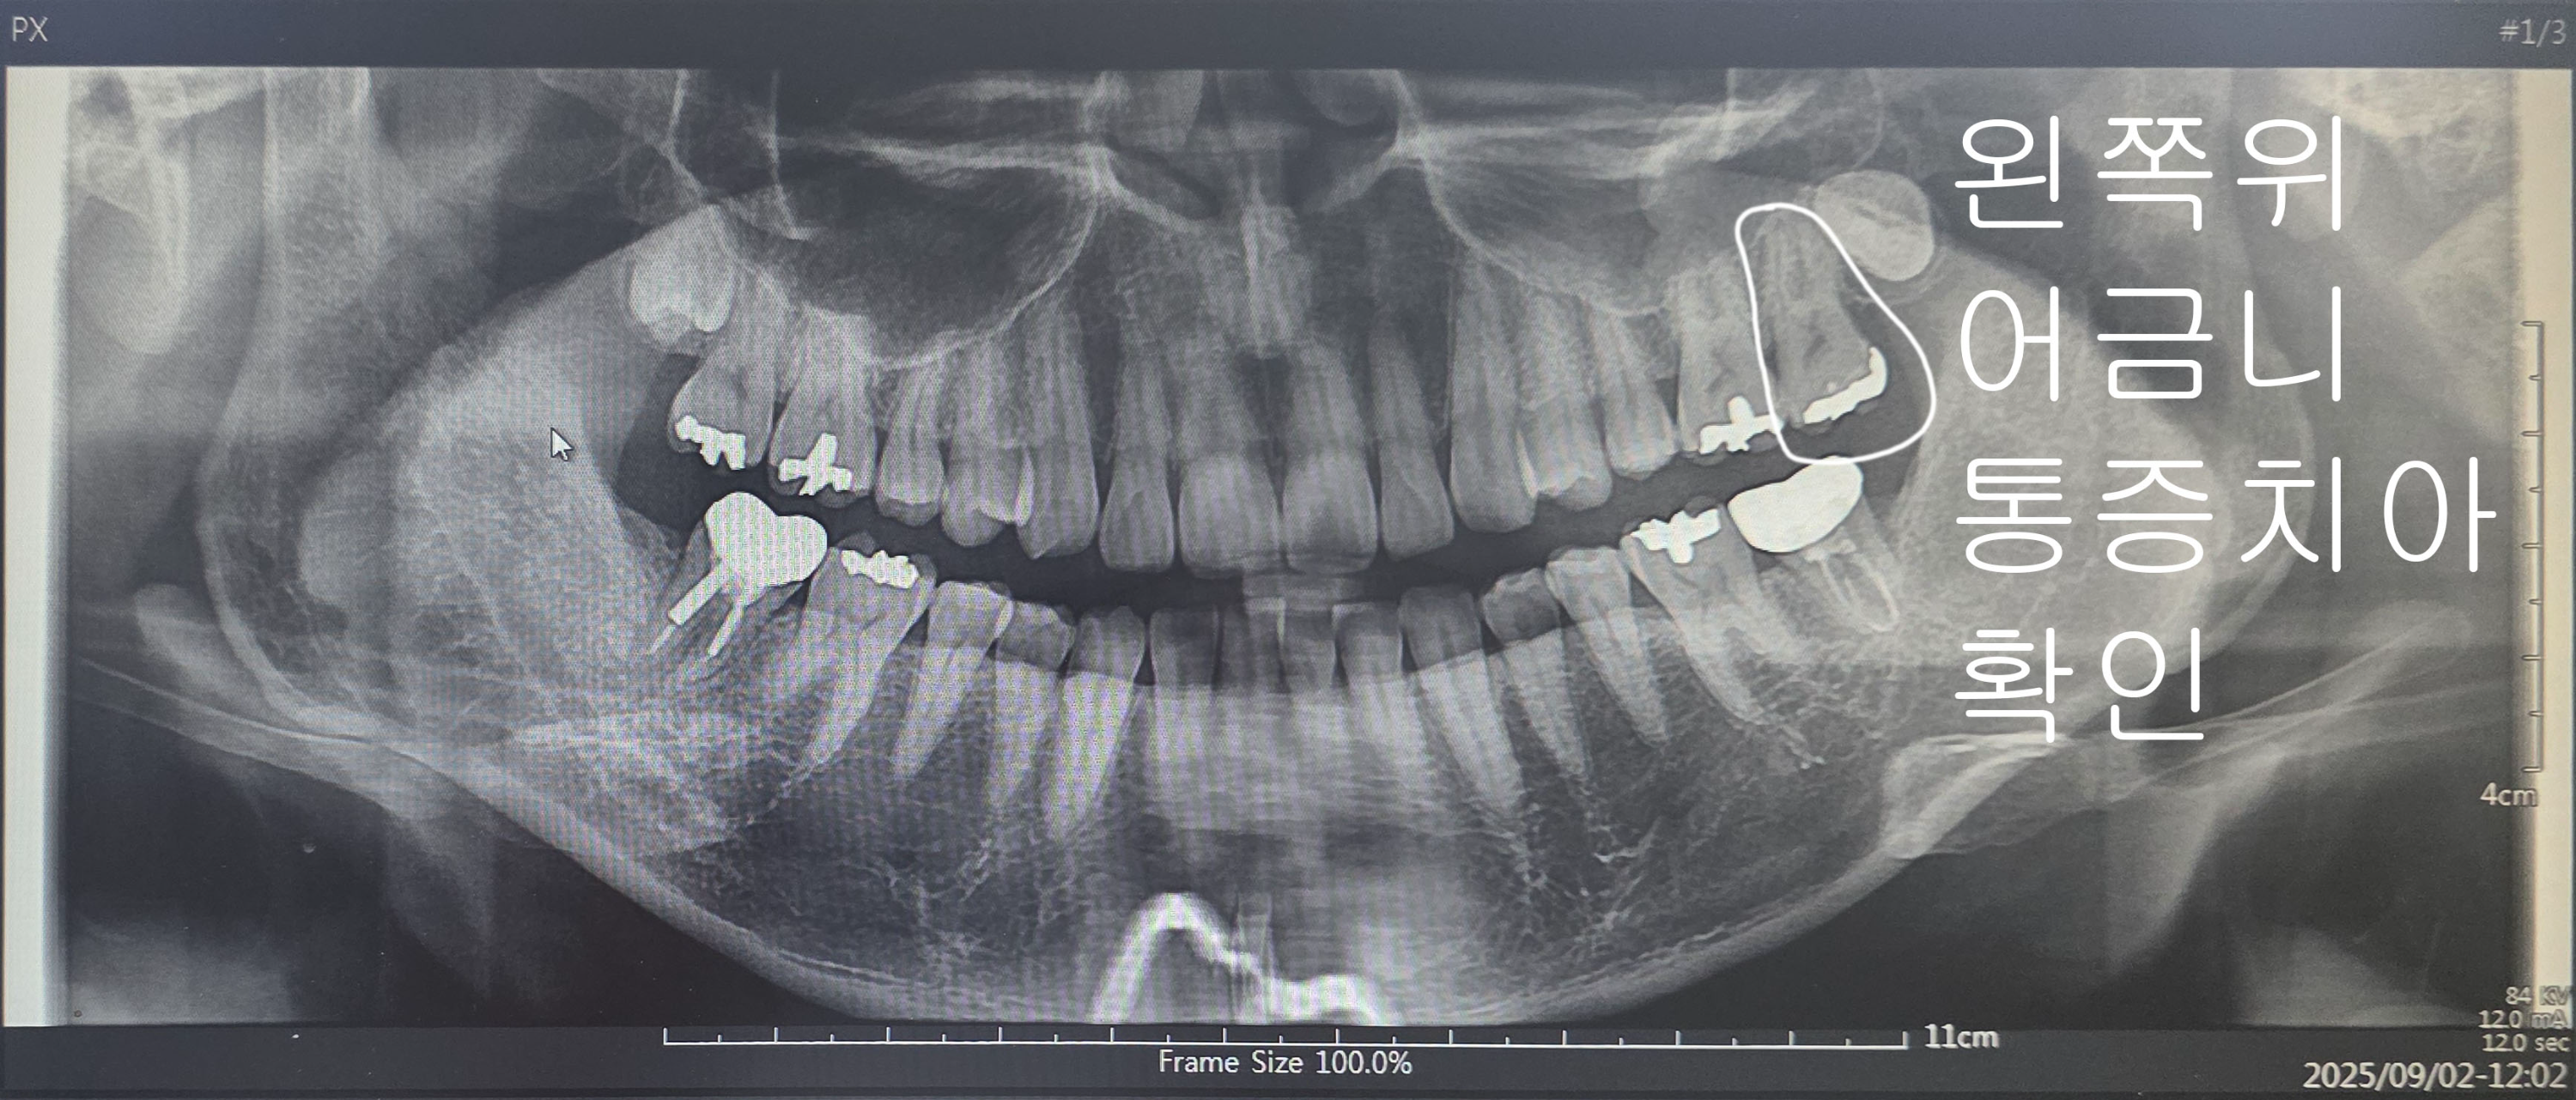

아침에 따신물을 마시는데 갑자기 왼쪽 어금니쪽 부근에 통증이 느껴졌습니다.

일단, 왼쪽 어금니쪽 부근의 통증이었어요!

하지만 아래가 아닌 위쪽인듯한 느낌을 받았었기에 참고하고 일단 병원부터 찾았습니다.

일단, 의심되는 거 3개 다 치료하자! 가 아니고 정확한 통증 치아를 찾아내고 치료를 시작했습니다.

신경이 많이 손상되었고 상태가 아주아주 안 좋은 상황이라고 하셔서 신경치료를 몇 번 더 했습니다.

마지막 신경치료까지 마친 치아 상태입니다. 저는 봐도 모르겠습니다.

뿌리까지 신경치료를 모두 잘 치료했다고 들었어요!